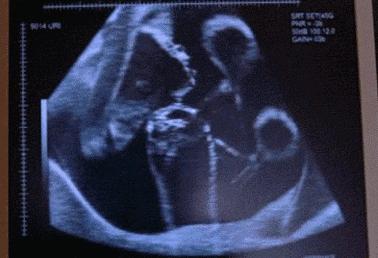

28岁的田女士与丈夫结婚已经6年了,记得在结婚那时,夫妻俩人就开始了造人计划并在不长就传来喜讯,可这样的欢乐没持续多久,在怀孕23周的时候,田女士肚子突然腹痛,而且阴道有出血的症状,家人赶紧把田女士送到医院,然而检查发现胎儿已经胎死腹中两周了。

这噩耗让夫妻俩难以接受,但是也无可奈何。直到一年后再次怀孕,为防意外再次出现,在得知怀孕后就辞职在家。可噩耗再次降临在她身上,宝宝又一次的胎死腹中,接一连二的打击让田女士崩溃了。

但是在给田女士做清宫手术时,发现她体内的指标有些异常,不仅血压高、甲状腺功能、血钾低,并且在怀孕后就出现皮肤紫纹、痔疮的症状,经一系列的检查,最终找到孩子死亡的原因—脑垂体微腺瘤。

医生表示脑垂体肿瘤一般是育龄妇女患上比较多,如果在得知患有脑垂体肿瘤的女性,一定要及时手术治疗。并且除了脑垂体微腺瘤的疾病使胎儿胎死腹中,孕妇在孕期也要关注这些隐患,才能保证宝宝的顺利降生。